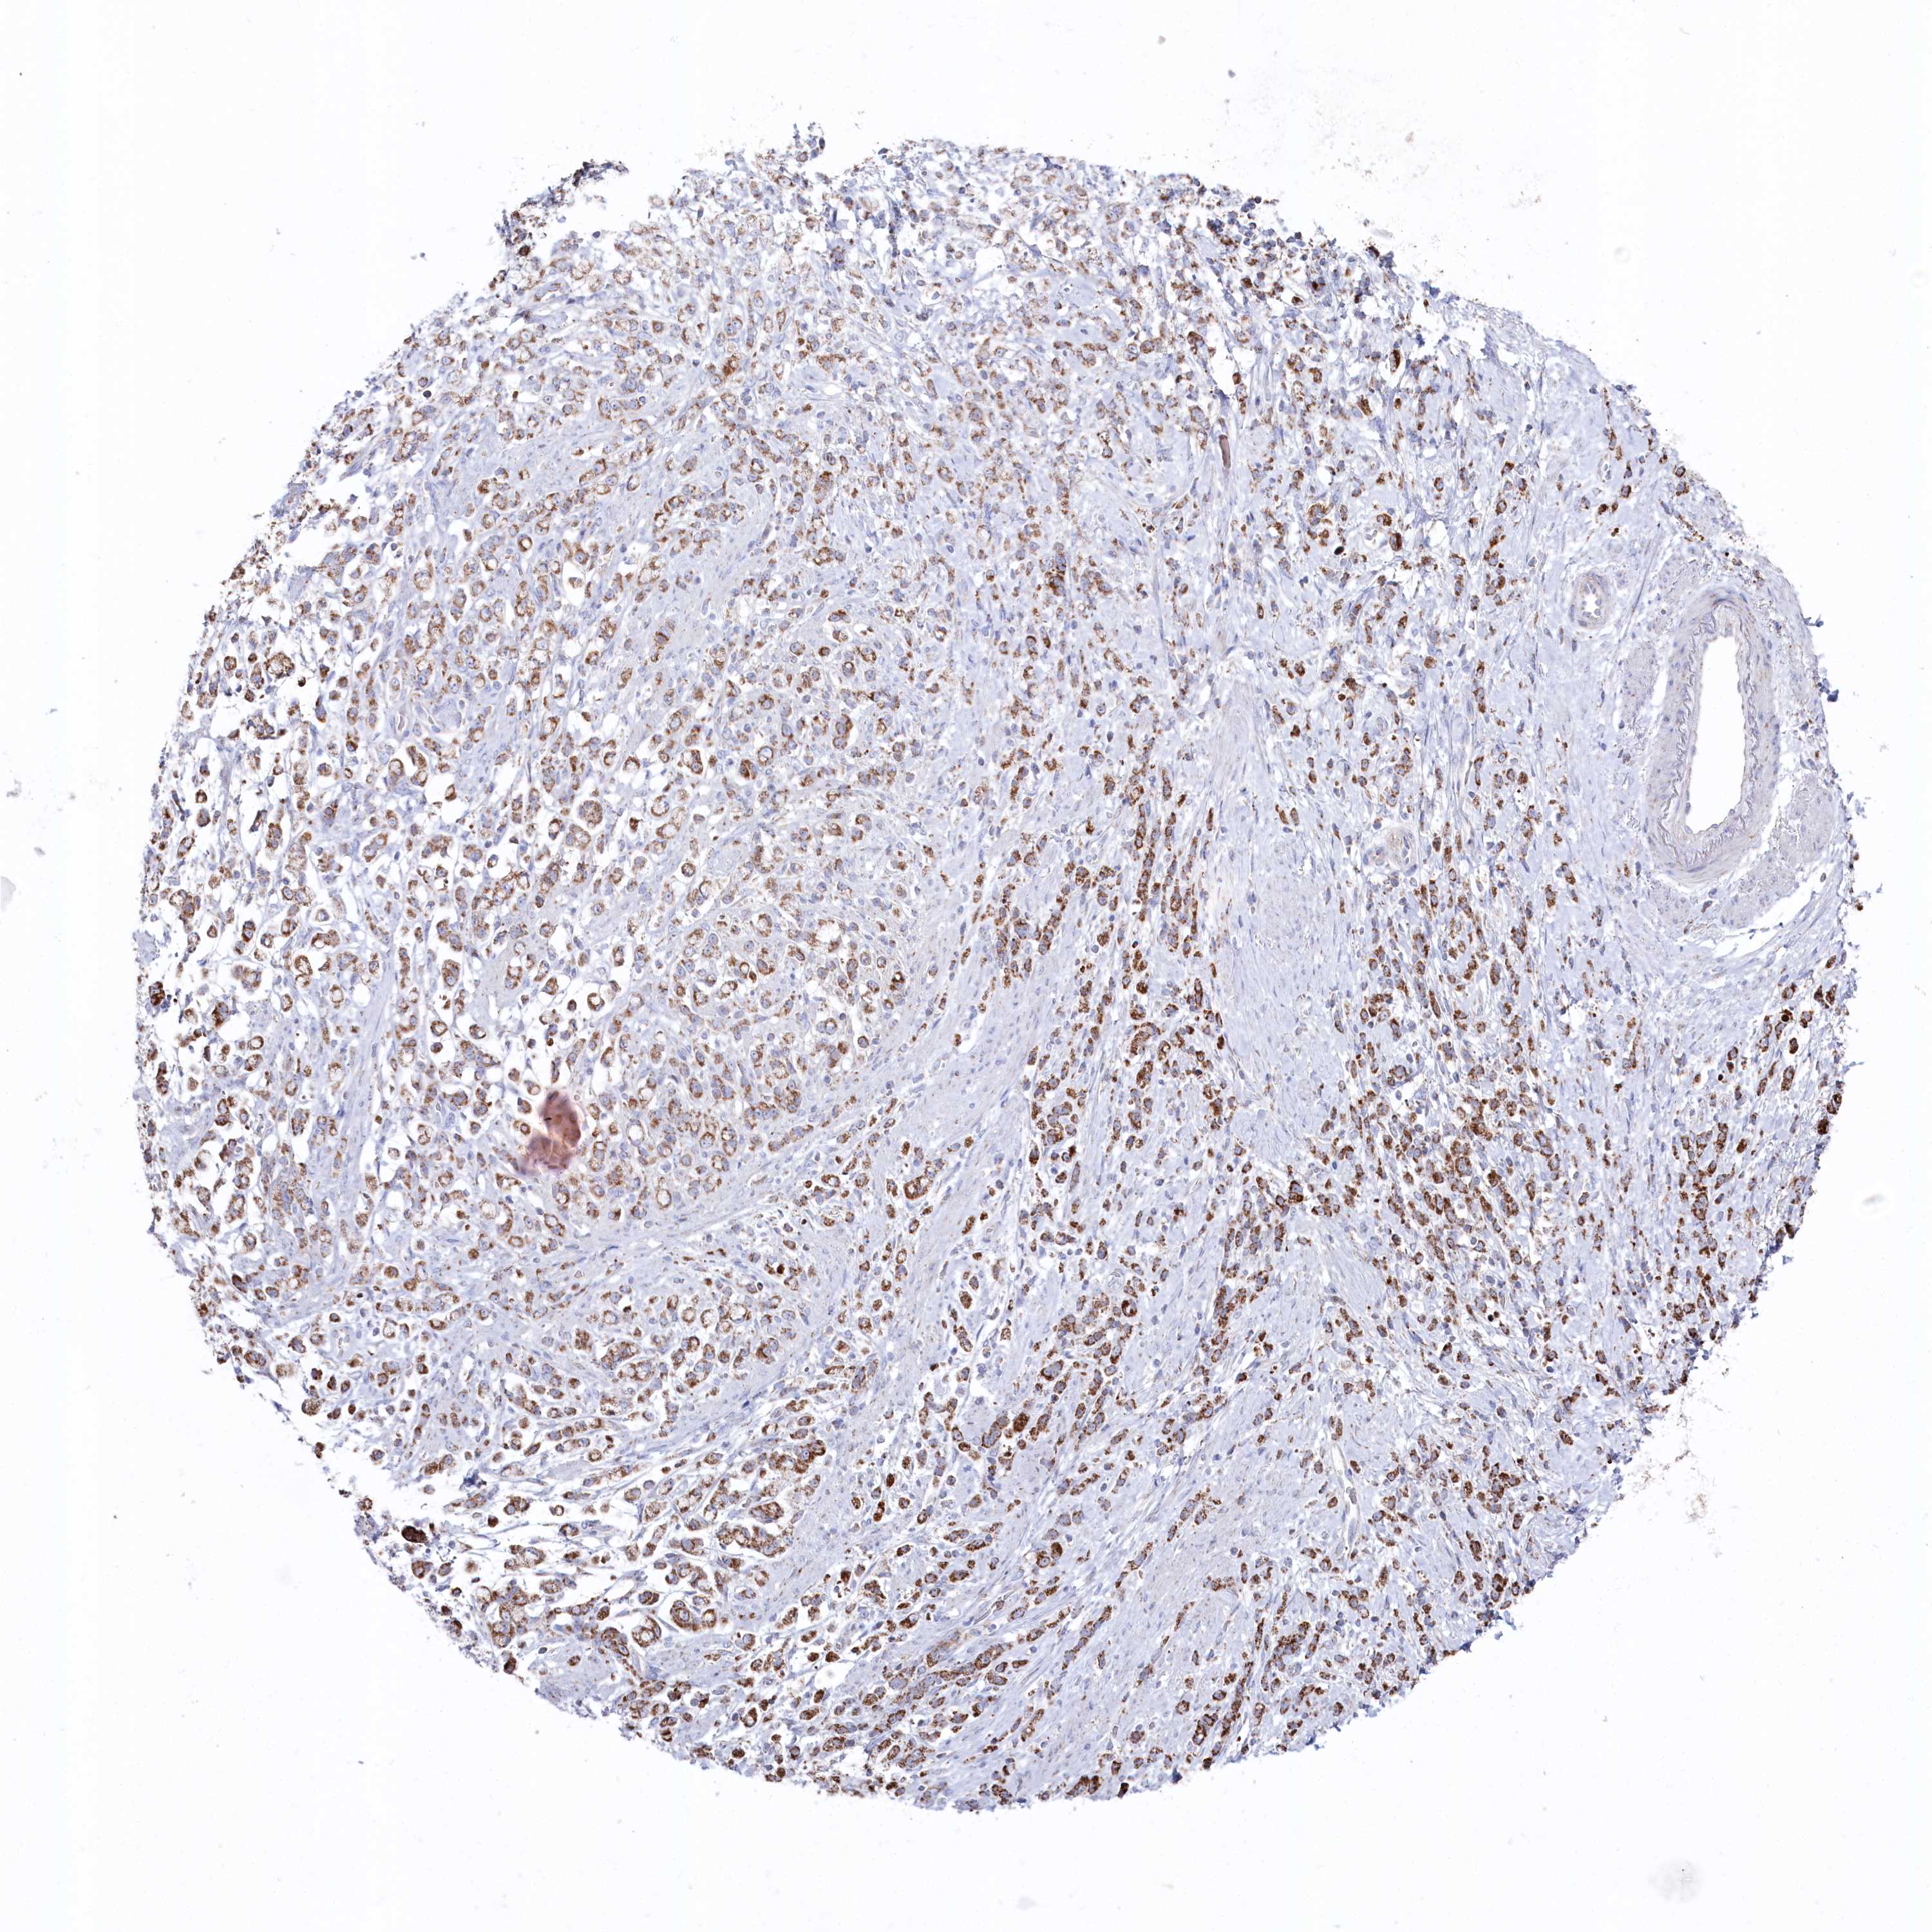

STOMACH CANCER - Protein expressioni

A mouse-over function shows sample information and annotation data. Click on an image to view it in a full screen mode. Samples can be filtered based on level of antibody staining by selecting one or several of the following categories: high, medium, low and not detected. The assay and annotation is described here.

Note that samples used for immunohistochemistry by the Human Protein Atlas do not correspond to samples in the TCGA dataset.

Antibody stainingi

Antibody staining in the annotated cell types in the current human tissue is reported as not detected, low, medium, or high, based on conventional immunohistochemistry profiling in selected tissues. This score is based on the combination of the staining intensity and fraction of stained cells.

Each image is clickable and will lead to virtual microscopy that enables deeper exploration of all samples and also displays staining intensity scores, fraction scores and subcellular localization as well as patient and tissue information for each sample.

Antibody HPA038608

Staining

High

Medium

Low

Not detected

Intensity

Strong

Moderate

Weak

Negative

Quantity

>75%

75%-25%

<25%

None

Location

Nuclear

Cytoplasmic/membranous

Cytoplasmic/membranous,nuclear

Adenocarcinoma, NOS

Adenocarcinoma, High grade